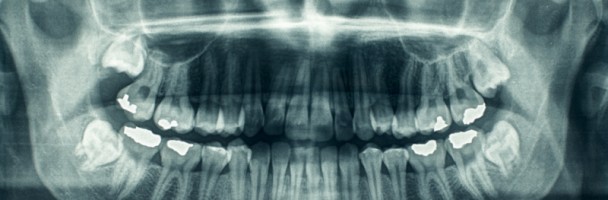

L’ortopantomografia, chiamata anche radiografia panoramica delle arcate dentarie, è una tecnica radiografica che produce un’immagine dei denti, delle arcate dentarie e delle ossa mascellari e mandibolari su un’unica pellicola.

L’ortopantomografia è un esame radiografico e quindi espone il paziente alle radiazioni ionizzanti: tuttavia la dose di raggi x che viene assorbita dal paziente per questo esame utilizzando un panoramico digitale è inferiore di molte volte rispetto a quanto viene somministrato eseguendo tutte le radiografie endo-orali necessarie per visualizzare separatamente tutti i gruppi di denti (panoramica di endo-orale).

L’ortopanoramica si esegue per lo studio panoramico dei denti, delle ossa alveolari e delle altre strutture radiopache che li circondano. Essa è fondamentale per un bilancio iniziale dello stato della bocca prima di un trattamento odontoiatrico: sulla sua scorta, il dentista potrà richiedere di eseguire le radiografie endo-orali di dettaglio necessarie per i gruppi di denti eventualmente da curare. E’ inoltre indispensabile per valutare lo stato della dentizione nei soggetti in età di sviluppo, per evidenziare eventuali malformazioni dentarie o denti inclusi e per ricercare lesioni ossee, infiammatorie, cistiche o tumorali a carico degli alveoli e degli altri costituenti scheletrici che circondano i denti.

L’esame ortopantomografico è eseguito, nella maggior parte dei casi, su indicazione odontoiatrica: tuttavia, la complessità delle strutture della bocca che sono studiate con questa indagine la rendono indicata anche in numerosi casi di patologie chirurgiche, oncologiche, otorinolaringoiatriche e maxillo-facciali.